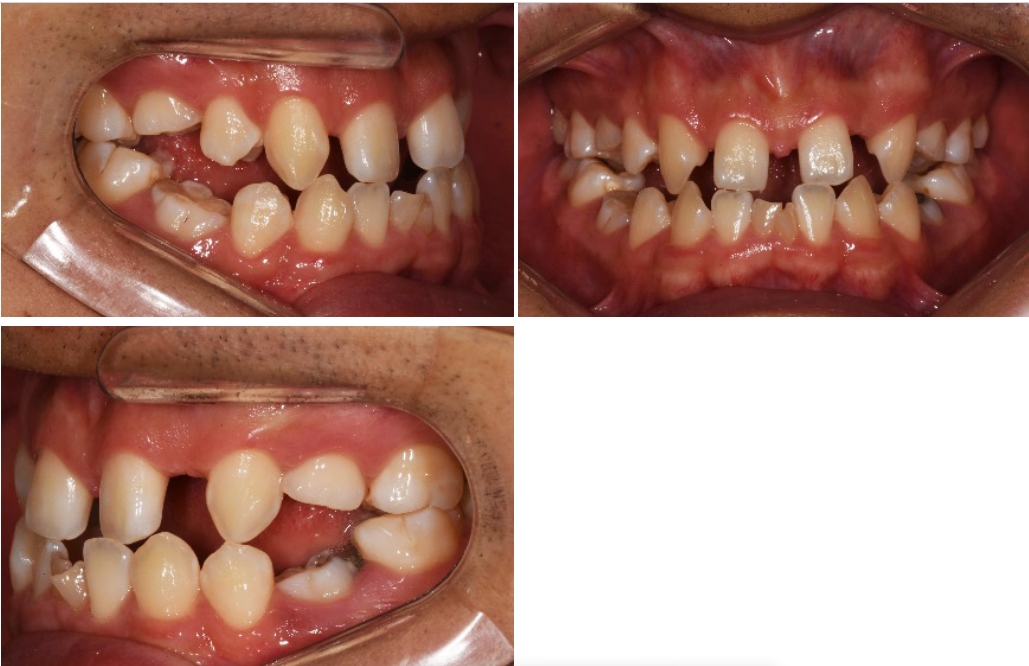

이 환자는 상악 양측 측절치와 양측 제1, 2 소구치, 하악 양측 제1, 2소구치, 양측 중절치의 결손을 가진 multiple congenital missing 환자입니다만 계속적 권유에도 불구하고 임플란트를 통한 전치부의 spacing 해결만을 원하였습니다.

때문에 상악에서만 부분교정을 통해 측절치 임플란트 식립 공간을 확보하기로 하였으며 동시에 상악 중절치의 반대교합 수정을 하기로 하였습니다.

양측 견치의 회전을 수정할 필요가 없고 중절치 이동을 위한 고정원으로 사용하기 위해 견치의 움직임을 최소화하였습니다.

견치 브라켓의 경우 원심쪽의 레진베이스를 두껍게 하여 견치 회전을 그대로 유지하기로 하였고 사전에 제작된 segmental archwire에 bracket slot이 평행하도록 setup하여 transferjig을 제작하였습니다.

중절치의 경우 양측 중절치가 근심으로 당겨지면서 치관의 mesial tipping이 예상되 므로 이를 상쇄해 주기 위해 bracket을 비뚤어지게 붙여서 중절치 치근이 서로 모아지는 방향이 되도록 배열하였습니다.

이어서 상악 양측 제1대구치에서 견치까지 설측에 resin wire splinting을 시행하여 견 치의 고정원을 강화하였습니다.